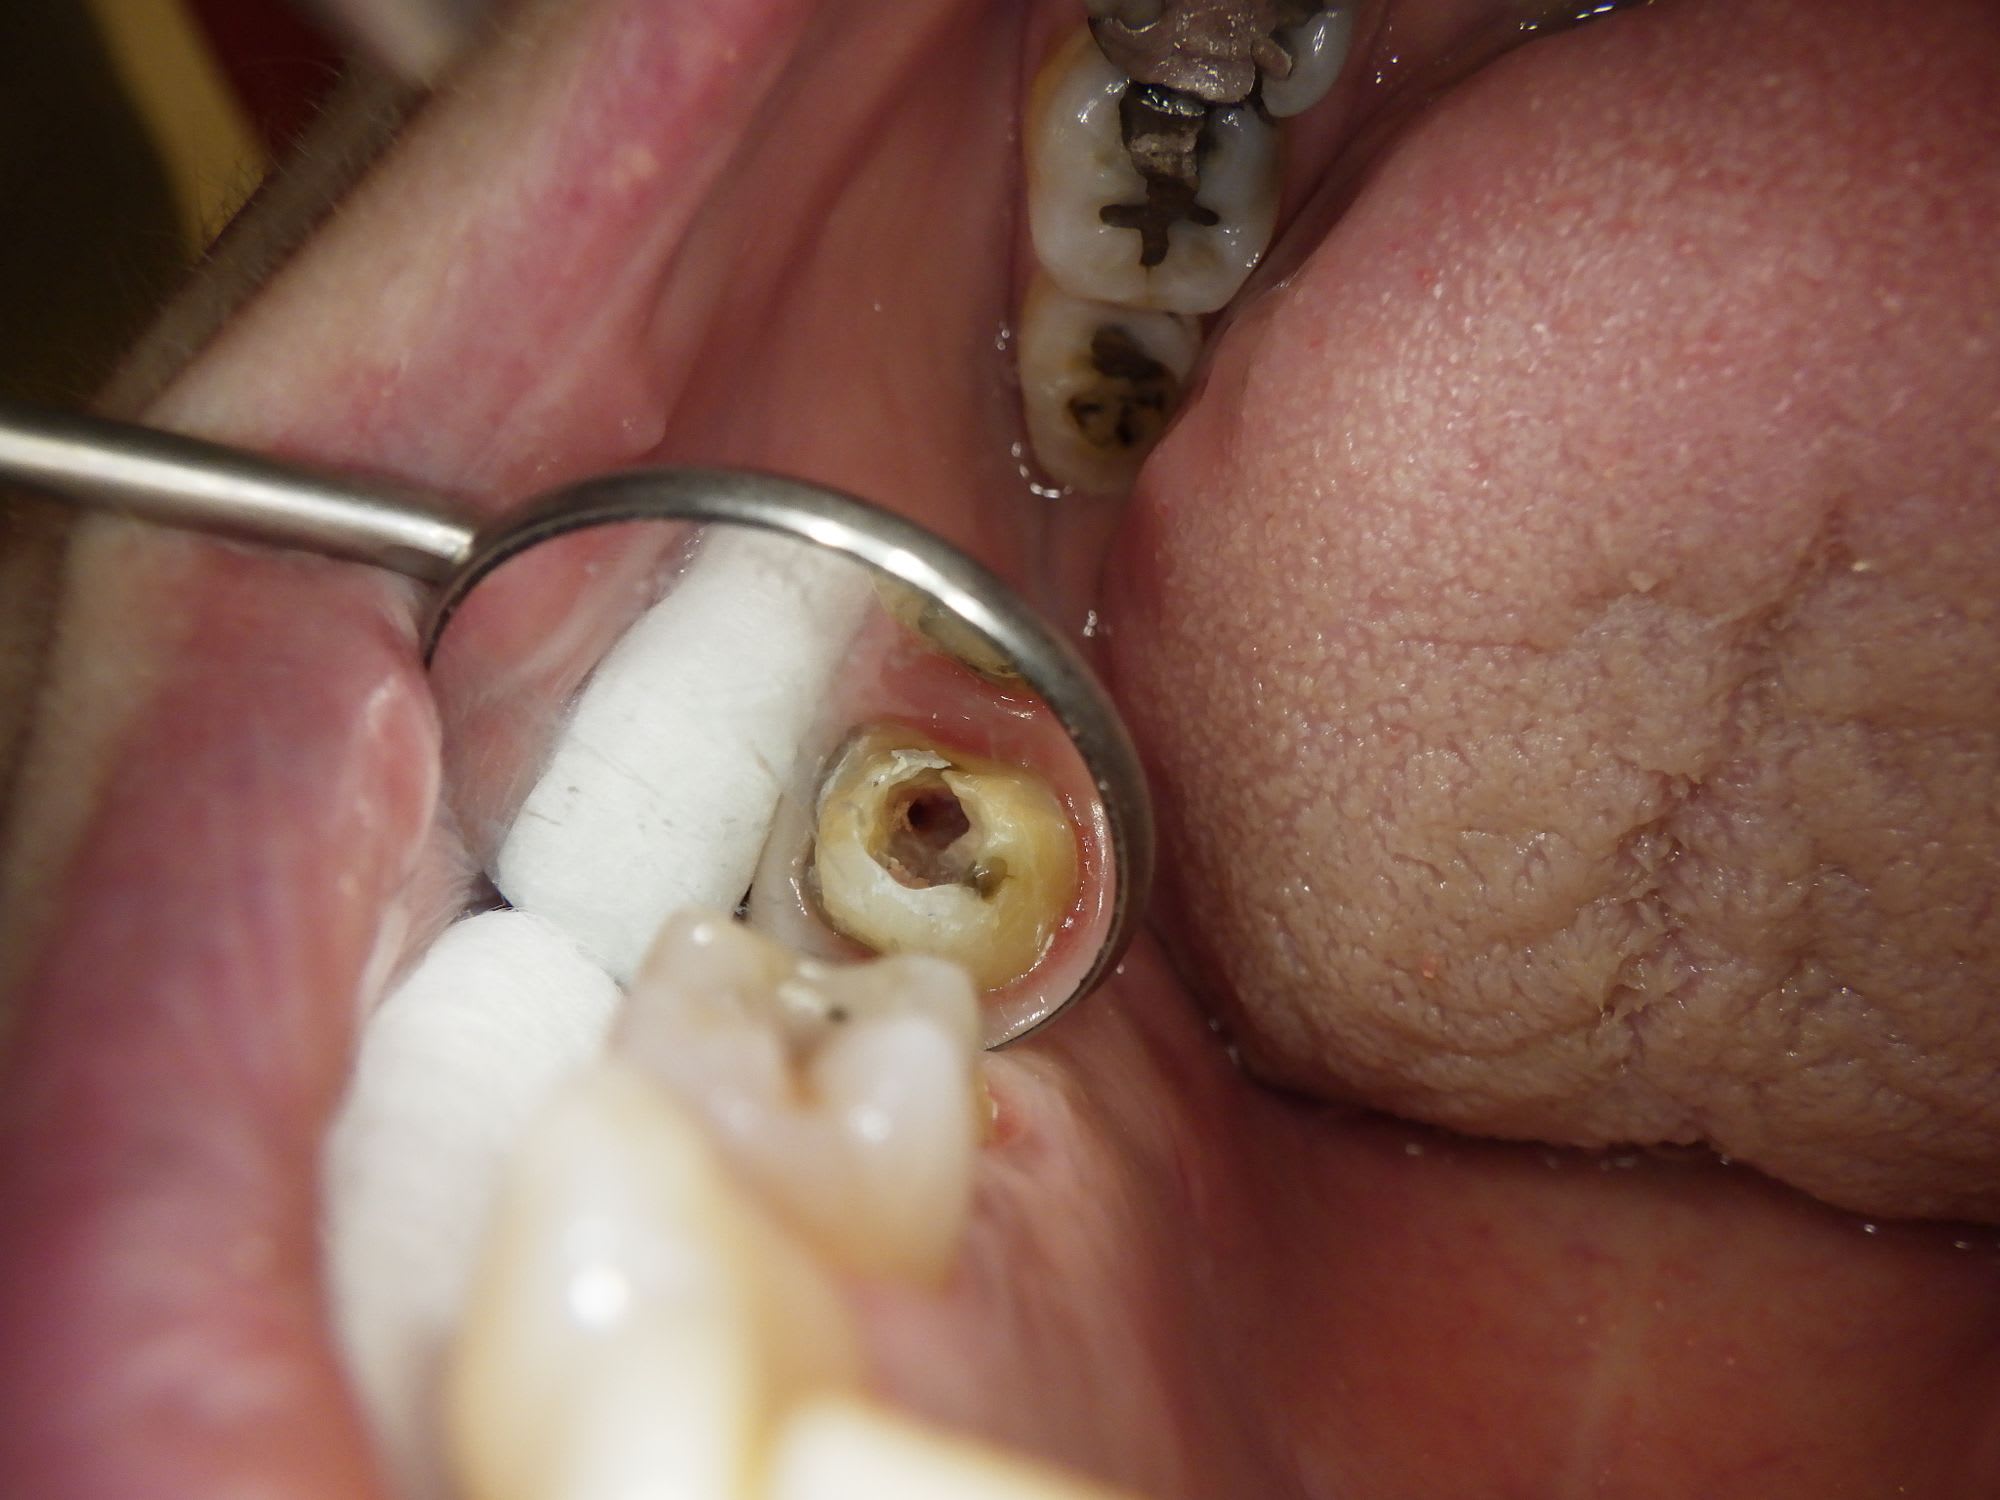

Voici une photo de la chambre , j'ai un peu cherché en palatin et vestibulaire une deuxième entrée, mais il n'y a rien.

Chercher une deuxième entrée en vestibulaire quand on voit sur cette coupe et sur la coupe horizontale que c’est le palatin qui n’est pas obturé, … les mots me manquent.

Pas de digue, c’est la cerise.

C'est bien en palatin que je suis allé cherché ce deuxième canal (cf la photo de la chambre) Je me retrouve très proche de la furcation et je n'ai pas trouvé l'entrée.

Au dessus tu dis que tu l’as cherché en vestibulaire et palatin : « Voici une photo de la chambre , j'ai un peu cherché en palatin et vestibulaire une deuxième entrée, mais il n'y a rien.«

Le MV2 n’est pas très proche de la furcation mais plutôt plus mésial que le MV1. Il est très visible à la radio et ne doit pas être bien compliqué à traiter, mais pour ça il faut s’en donner les moyens et ça commence par la digue.

@DonChico - Pas le prendre mal, mais je suis surpris que personne n'ai encore critiqué ta cavité d'accès.

Si ce qu’on voit est le MV1 désobturé, le MV2 est à peu de chose près là où est ta flèche verte. Son entrée est souvent plus apicale. Le trouver est une chose, le négocier une autre, souvent bien chronophage.

Avec de la lumière, du grossissement, une cale, une digue étanche, une bonne assistante, tout est plus facile.

L'histoire de l'entrée du canal plus palatin et mésial , c'est ce que je me suis dit aussi en voyant ma photo de la cavité d'accès.

Mais quand je vois à quelle profondeur je suis au niveau de la racine , je me suis dit que je serai retombé sur le canal MV2 sans jouer avec la zone de furcation de la molaire.

C'est toujours stressant d'aller à la pêche dans ces zones là quand il y a une calcification de la chambre.